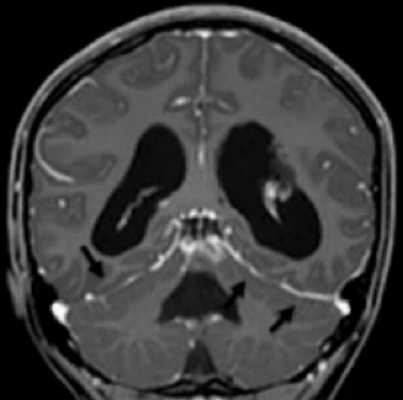

Криптококковый менингит на фоне ВИЧ-инфекции на МР-снимках

Пневмококковый менингит с миелитом (патологические изменения указаны стрелками)

Рентгенологи проводят расшифровку снимков, исходя из интенсивности сигнала от определенных тканей при применении разных режимов сканирования. МРТ-признаками менингита считают:

- изоинтенсивный ответ от экссудата на Т1 ВИ;

- гиперинтенсивный сигнал от тех же зон на Т2 ВИ;

- признаки гидроцефалии или повышение интенсивности импульсов от борозд и цистерн;

- характерное окрашивание структур, окружающих гнойники, после контрастирования;

- гиперинтенсивный сигнал от абсцессов, визуально заметная капсула;

- сужение просвета артерий или окклюзионные изменения при ангиорежиме сканирования;

- тромбоз вен при магнитно-резонансной венографии.